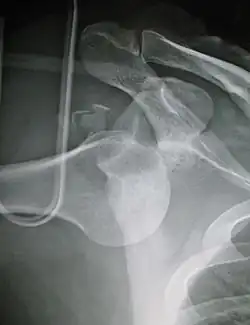

Lightbulb sign indicative of posterior shoulder dislocation shown on the left. On the right, the same shoulder after reduction.

Posterior dislocations are uncommon, and are typically due to the muscle contraction from electric shock or seizure.[6] They may be caused by strength imbalance of the rotator cuff muscles. People with dislocated shoulders typically present holding their arm internally rotated and adducted, and exhibiting flattening of the anterior shoulder with a prominent coracoid process.

Posterior dislocations may go unrecognized, especially in an elderly person[15] and in people who are in the state of unconscious trauma.[16] An average interval of 1 year was noted between injury and diagnosis in a series of 40 people.[17]